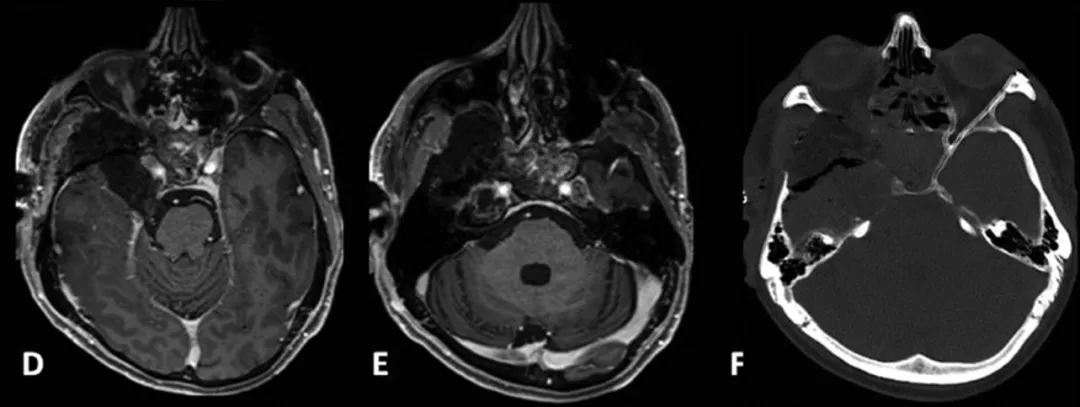

患者术后影像。(D,E)术后增强MR显示肿瘤全切。(F)术后轴位CT扫描显示用于闭合的自体脂肪移植。

术后MRI显示肿瘤完全切除。患者右侧角膜炎在10天内消退,V3感觉减退在2个月后改善。